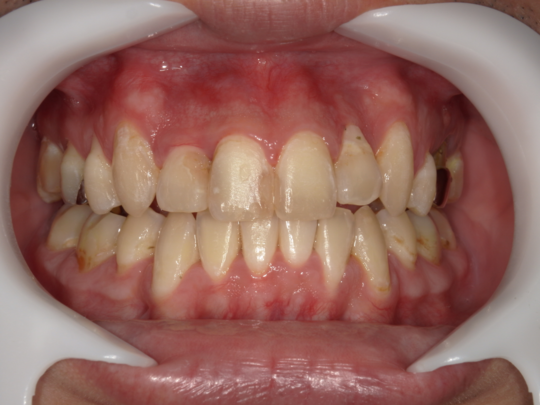

でこぼこの歯並びの矯正(叢生)(八重歯)

治療前

治療説明 歯科矯正でも目立ちにくい矯正方法であるマウスピース矯正で治療しました

治療期間 2年

治療費用498000 円